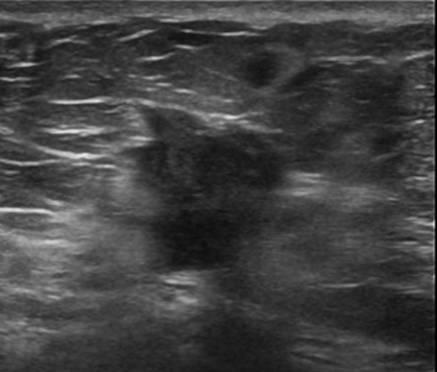

Ung thư vú - Ảnh 3

Ung thư vú

» Thông tin: Nữ giới – 72 tuổi.

» Lâm sàng: Khối tuyến vú.